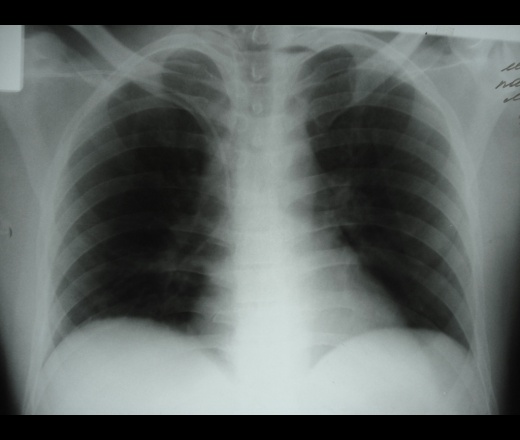

пациент с хирургии, лежит с переломом костей таза и забрюшинной гематомой. начиналось все неплохо. Потом через пару дней вот так стало:

пациент с хирургии, лежит с переломом костей таза и забрюшинной гематомой. начиналось все неплохо. Потом через пару дней вот так стало:  снимки лежа

снимки лежа

хирурги приходили, подозревают медиастинит, пациент оперирован по поводу спленэктомии, была забрюшинная гематома (травма). Боковую не делали, пациент из перелома костей таза не поворачивается. на Узи небольшое кол-во жидкости справа.

какие будут мнения Уважаемые коллеги. Последний снимок полустоя.

Ателектаз н/д справа. Бронхоскопия.

Правая боковая, совсем, в плане диагностики, была-бы не лишней, а весьма уместной.